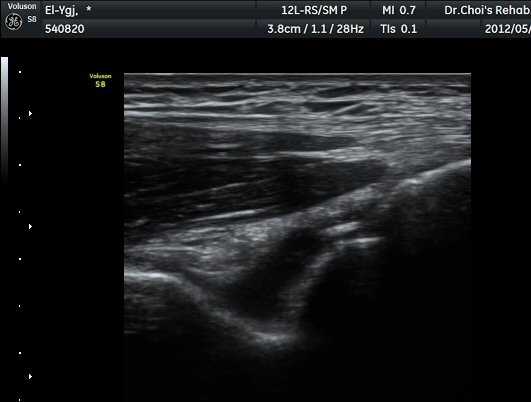

ÆÈ²ÞÄ¡ ¿ÜÃø Á¾´Ü¸é°Ë»ç¿¡¼­ ¼ÒµÎ ¾ÕÂÊ¿¡ ¼ö¾×Àú·ù°¡ °üÂûµÈ´Ù(±×¸² 1).